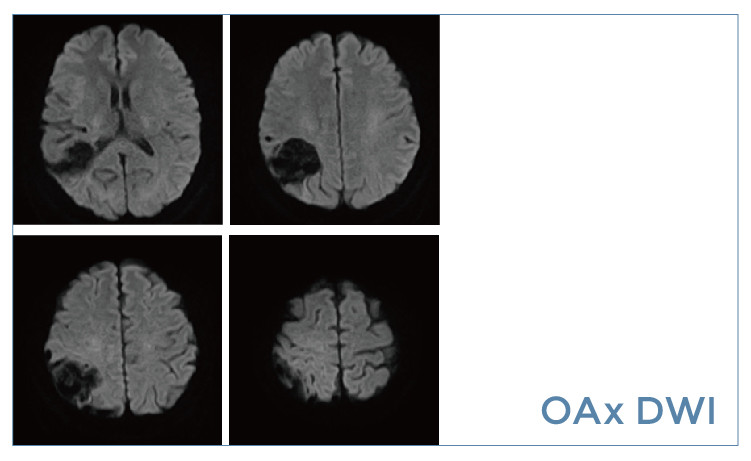

【朗润影像档案】20190531磁共振影像病例结果讨论

2.jpg3.jpg